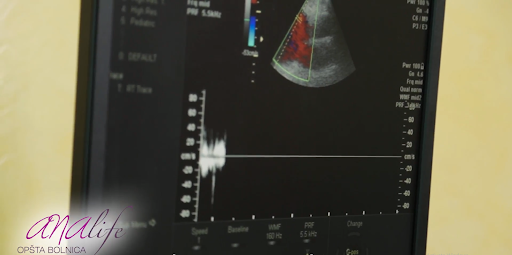

Uzimajući u obzir širok spektar bolesti koje daju isti simptom-zamaranje, neophodno je obaviti internistički i kardiološki pregled radi utvrđivanja uzroka tegoba. Dodatne metode koje nam omogućavaju postavljanje tačne dijagnoze su analize krvi ( vrstu analize indikuje kardiolog nakon obavljenog kliničkog pregleda), ultrazvučni pregled srca, radiografija srca i pluća. Dijagnostički pristup se određuje individualno za svakog pacijenta.